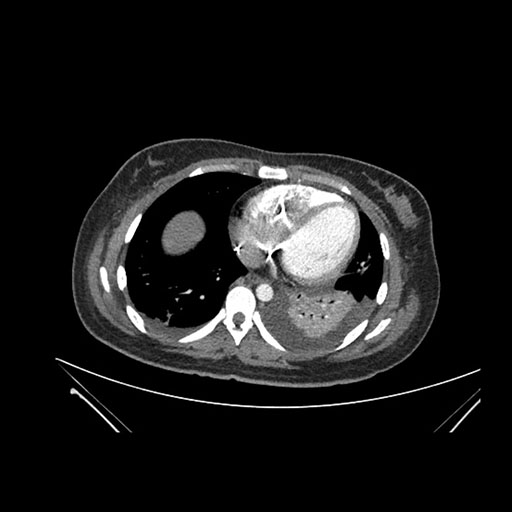

Imaging Analysis

Look through the patient's CT scan to identify any areas of concern for the necessary procedure.

Coronal Arterial